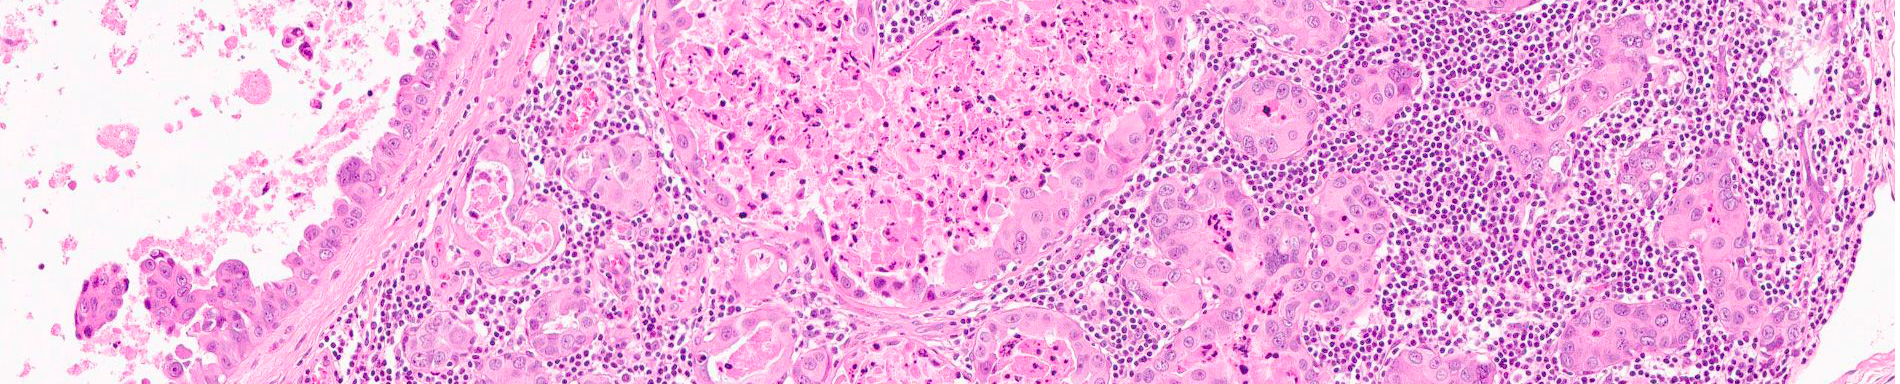

Procedimiento diagnóstico y/o terapéutico que consiste en la visualización por vía endoscópica de la laringe.

Permite complementar, entre otros, el diagnóstico de laringitis crónica -frecuente en fumadores- y de la patología tumoral benigna o maligna.

Posibilita tomar biopsias, planificar una cirugía más extensa o realizar una resección total de la lesión.